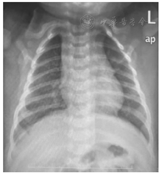

病例2 患儿,男,2个月9 d,因"咳嗽12 d"于2019年3月6日第1次入院。入院12 d前出现零星咳嗽,予口服中草药(具体不详)处理后,症状未见好转,并逐渐加重,呈痉挛性鸡鸣样咳嗽,1周前来我院急诊予雾化、口服阿奇霉素治疗后,咳嗽无好转,并查百日咳DNA检测回报(+),予收住我院。好转出院1周后,患儿痉挛性咳嗽再次加重(24 h痉挛性咳嗽20余阵,每阵约10~20声,剧咳时伴呕奶数次,无发绀),于2019年3月25日第2次住院治疗。第1次入院查体:T 36.5 ℃,P 127次/min,R 32次/min,体重7.0 kg。精神尚可,前囟平软,无鼻煽及点头呼吸,三凹征阴性,肺部呼吸音粗,未闻及干湿性啰音;心腹查体无阳性体征。入院2 d前查血常规:WBC 11.7×109/L,N 15.9%,L 69.8%,Hb 104 g/L,PLT 244×109/L;百日咳DNA检测(+)。入院诊断:百日咳。辅助检查:入院当天血常规:WBC 13.7×109/L,N 14.9%,L 73.9%,Hb 104 g/L,PLT 244×109/L;CRP 0.8 mg/L;肝肾心功能基本正常。X线胸片(图2)提示:拟支气管肺炎X线征。第2次入院第1天血常规:WBC 10.1×109/L,N 11.6%,L 68.2%,Hb 123 g/L,PLT 239×109/L;CRP 0.8 mg/L;肝肾心功能未见异常;第2次入院第24天血常规:WBC 11.6×109/L,N 28.3%,L 73.5%,Hb 114.0 g/L,PLT 255×109/L;CRP 7.0 mg/L。第1次入院治疗:予阿奇霉素抗感染、布地奈德联合异丙托溴铵雾化每6小时1次治疗,入院当天经家长签字同意后予加用大剂量盐酸氨溴索注射液10 mg/(kg·次)每天2次(药物生产厂家同病例1),并加入5%葡萄糖水50 ml静脉滴注。住院第7天痉挛性咳嗽明显缓解(24 h痉挛性咳嗽5~10阵,每阵5~10声,无发绀及呕吐);住院第10天改用口服盐酸氨溴索片(15 mg/次,每天3次)。住院第12天痉挛性咳嗽症状好转出院(24 h痉挛性咳嗽小于5阵,每阵3~4声,无发绀及呕吐)。第2次入院后再次予加用大剂量盐酸氨溴索[10 mg/(kg·次),每天2次]祛痰。再次住院第7天后患儿痉挛性咳嗽再次明显缓解;住院第11天予盐酸氨溴索减量至[5 mg/(kg·次),每天2次];治疗2周后再次改用口服盐酸氨溴索片(15 mg/次,每天3次);住院第20天患儿痉挛性咳嗽再次加重(24 h痉挛性咳嗽20余阵,每阵约10余声,剧咳时伴呕奶数次,无发绀)。予口服盐酸氨溴索片增加至(30 mg/次,每天3次),痉挛性咳嗽仍无缓解。治疗第22天再次予加用大剂量盐酸氨溴索[10 mg/(kg·次),每天2次]祛痰,并予丙种球蛋白(2.5 g)调节免疫止咳后,痉挛性咳嗽明显好转(24 h痉挛性咳嗽5~7阵,每阵5~6声,无发绀及呕吐)。治疗第36天零星咳嗽,无呈痉挛性咳嗽,好转出院,两次住院期间无全身皮疹、腹泻、休克等过敏表现,出院诊断:百日咳肺炎。出院后2周后电话随访:患儿零星咳嗽,1~2声/d,无再痉挛性咳嗽,一般情况可。